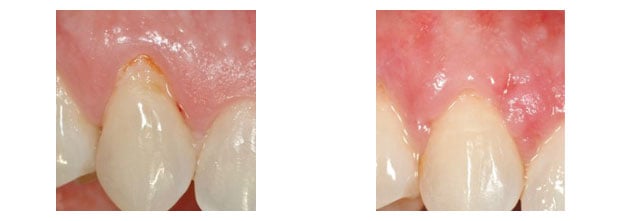

Esthetic crown lengthening

Recession around incisors

Following procedure to cover gingival recession